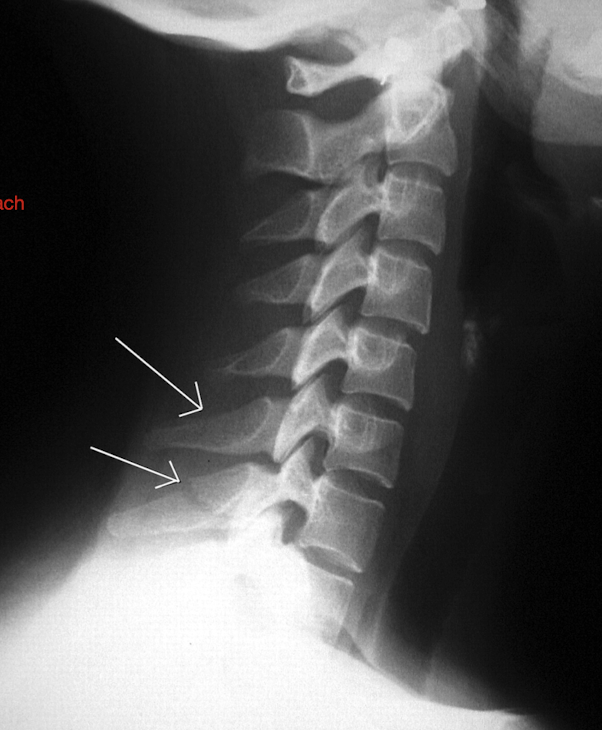

Label these 4 Lines? (C/S)

Notice: Post Vertebrae Intact, Ant Vertebrae w Fx